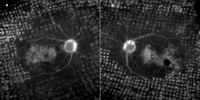

En ocasiones, la fuga de contraste precoz desde los capilares retinianos puede ser tan profusa que produzca un retraso en la tinción del árbol venoso, lo que ha sido interpretado como un retraso arteriovenoso

19, aunque se trata más bien de una falta de contraste que de un verdadero enlentecimiento del flujo sanguíneo. Este pseudorretraso venoso que aparece en las capilaritis profusas, con impregnación hiperfluorescente del neuroepitelio edematoso circundante, puede observarse, entre otras uveítis posteriores, en la coriorretinopatía en perdigonada y en la enfermedad de Behçet (

Figura 1).

Figura 1. Coriorretinopatía en perdigonada. Transmisión de la hiperfluorescencia coriocapilar en fases precoces por atrofia central (a y b). Pseudorretraso del llenado venoso por capilaritis difusa con fuga masiva del contraste en fase venosa (c y d).